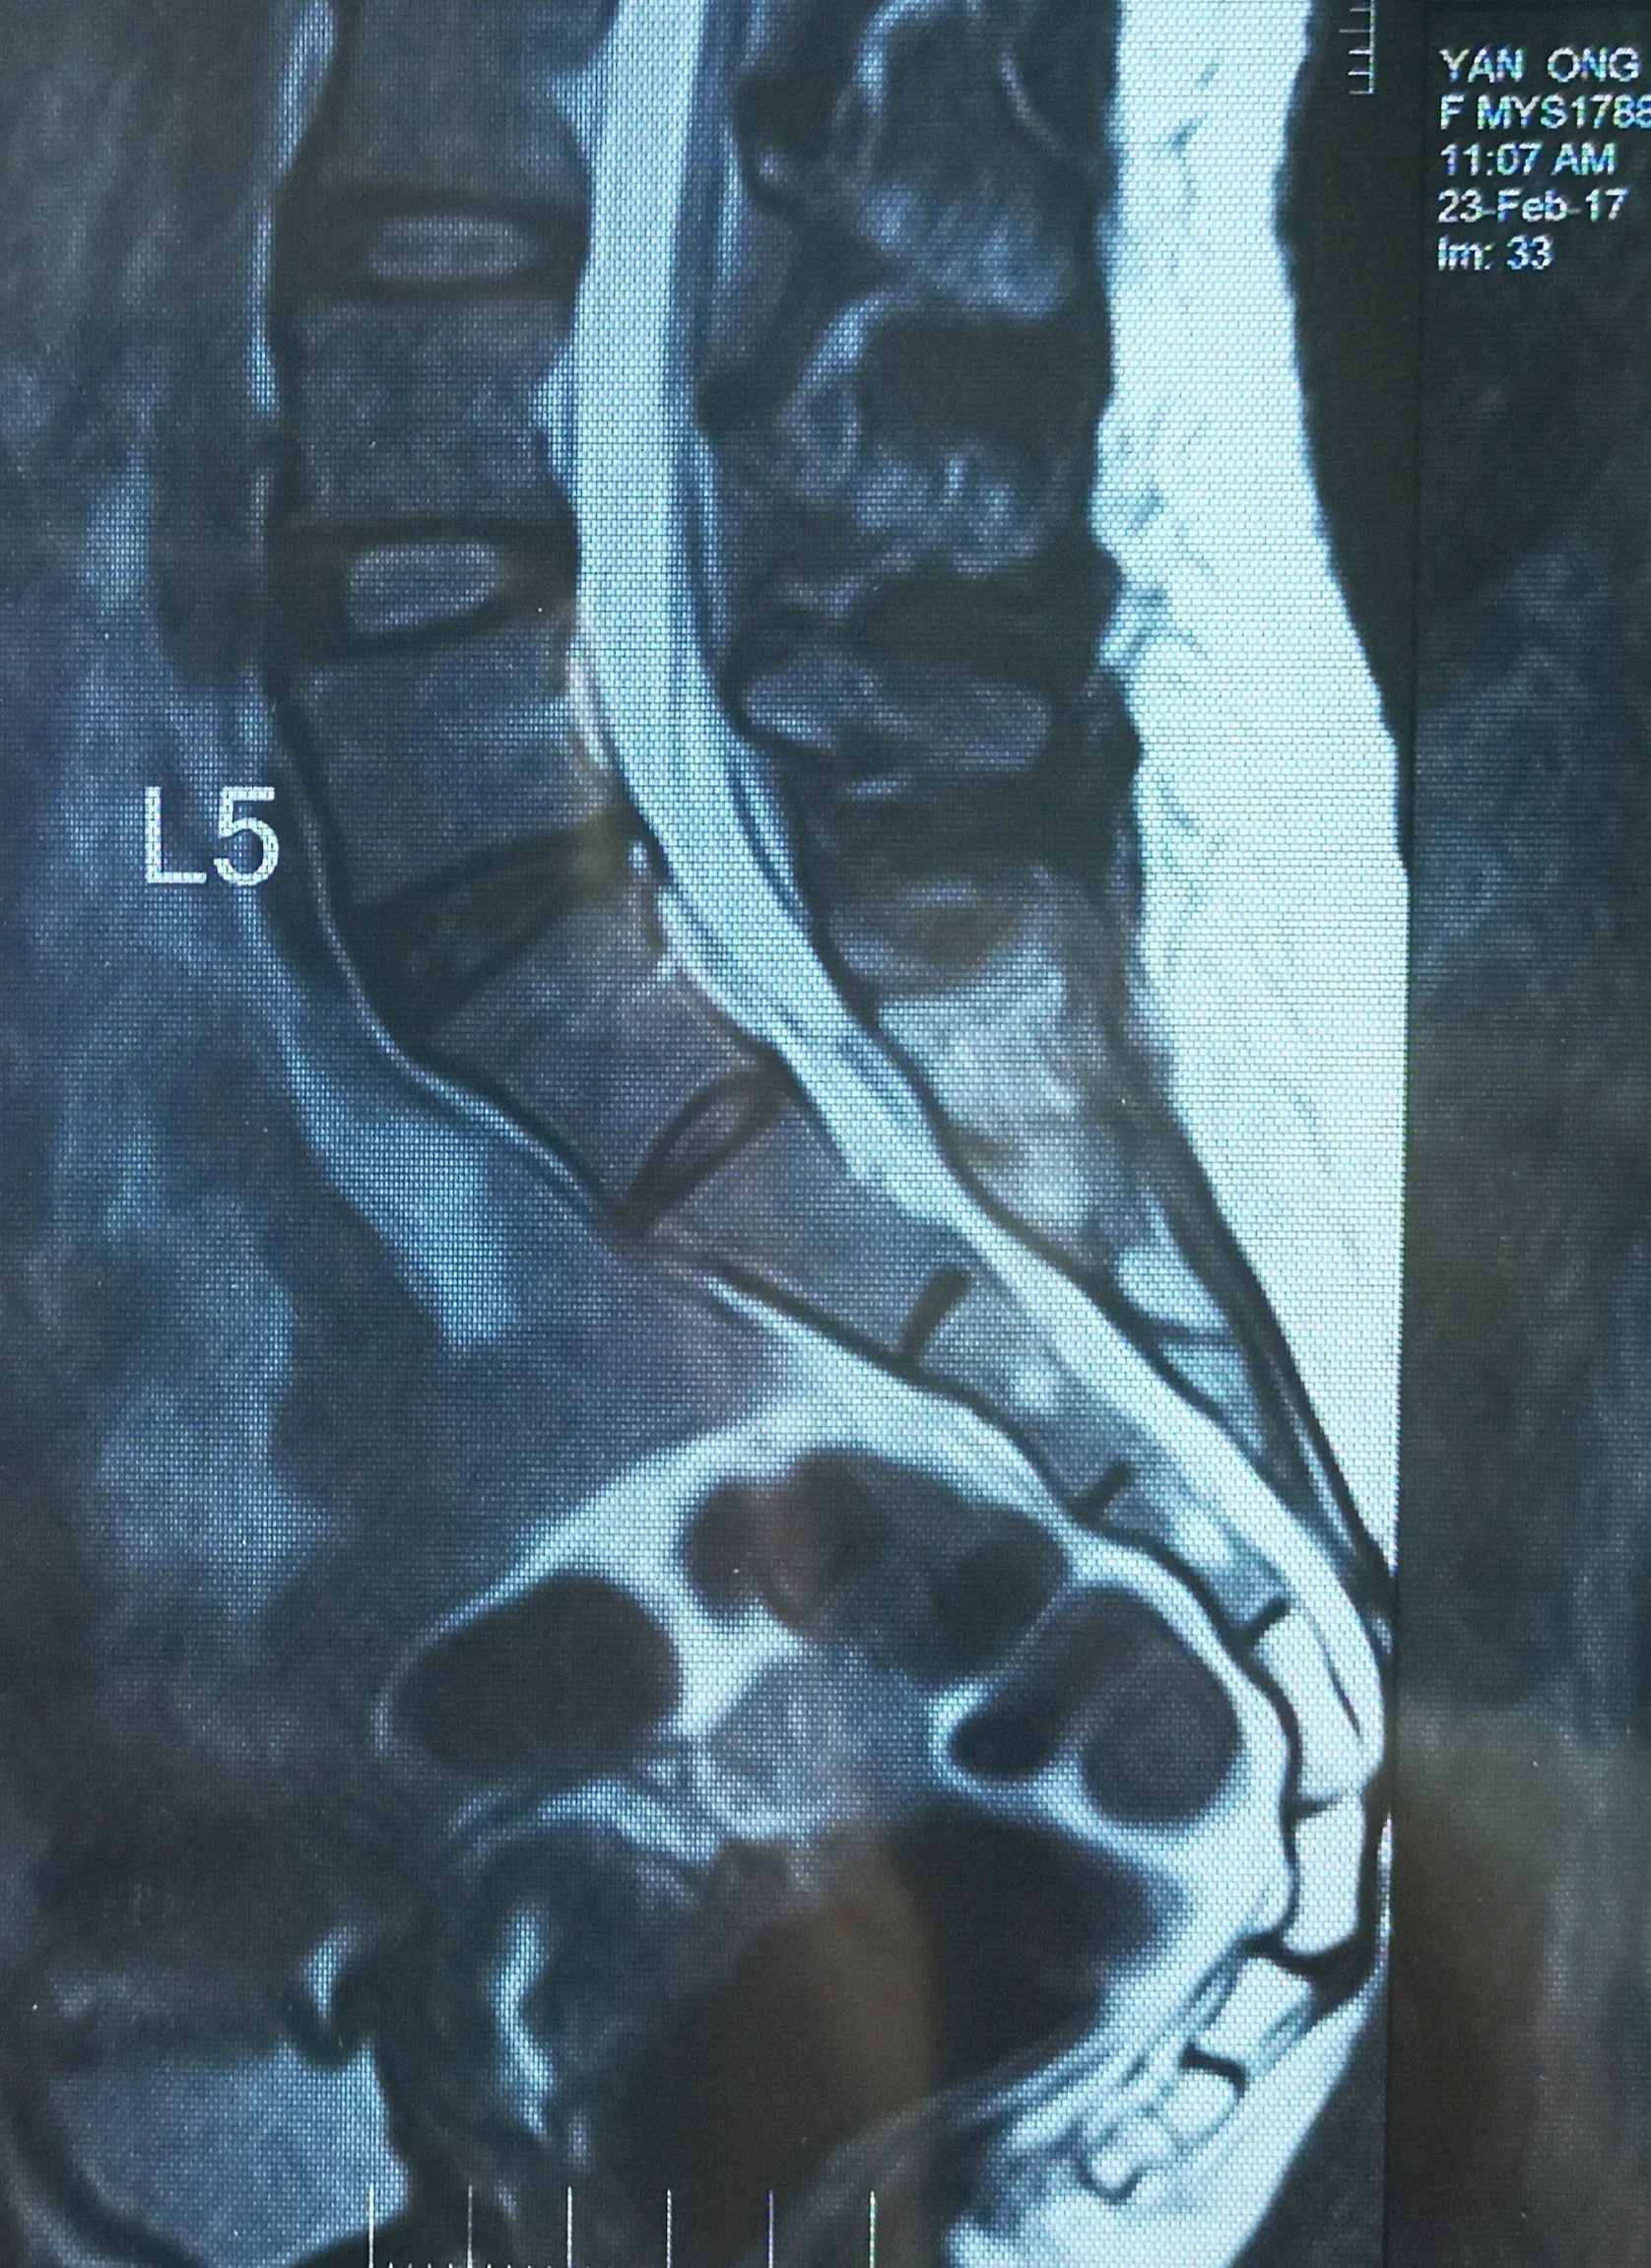

Little that I know at the time, it would lead to 7 years of dealing with pain and something I have come to accept will require me to manage daily for the rest of my life. Each year that I suffered the frustration, sadness and anger grew. Eventually, I discovered in an MRI, a herniated disc in the lower back completed the other end of this break.

MRI 1 in 2014. Posterocentral herniation with annulus tear indenting thecae sac & nerve roots. There’s no pain like nerve pain!